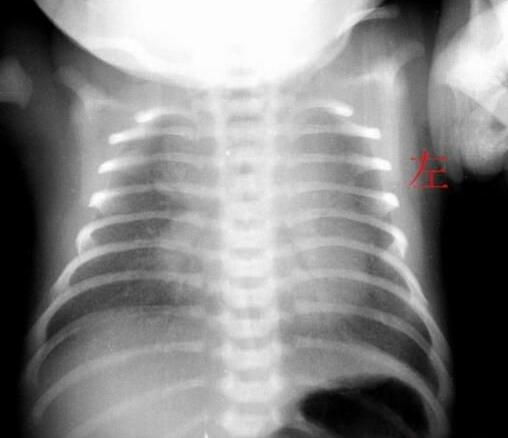

在胸部X线检查中,可以看到新生儿肺透明膜病具有特征性表现,按病情轻重可分四级。

第一级为细粟粒状毛玻璃样阴影,两肺透亮度减低;

第二级除粟粒阴影外可见超出心影的空支气管影;

第三级除上述影像外,心缘与隔缘模糊;

第四级为广泛的白色阴影称"白色肺",其中有黑色的秃叶树枝状空支气管树影由肺门向外周放射伸展至末梢气道,形成"支气管充气征"。用高压氧通入肺内,X线变化可获改善。